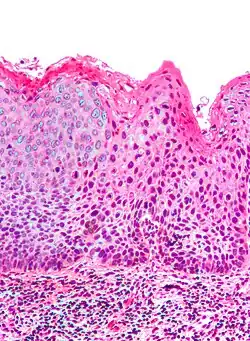

Micrograph of vulvar intraepithelial neoplasia III. H&E stain.

Micrograph of differentiated vulvar intraepithelial neoplasia. H&E stain.